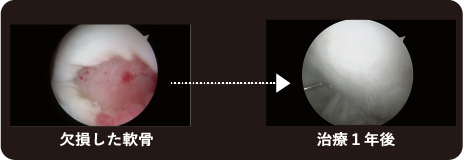

「自家培養軟骨」移植後の6カ月〜2年の間を「成熟期」といいます。術後1年程度経つと「自家培養軟骨」の硬さは「消しゴム」程度になり、さらに硬度を増していきます。